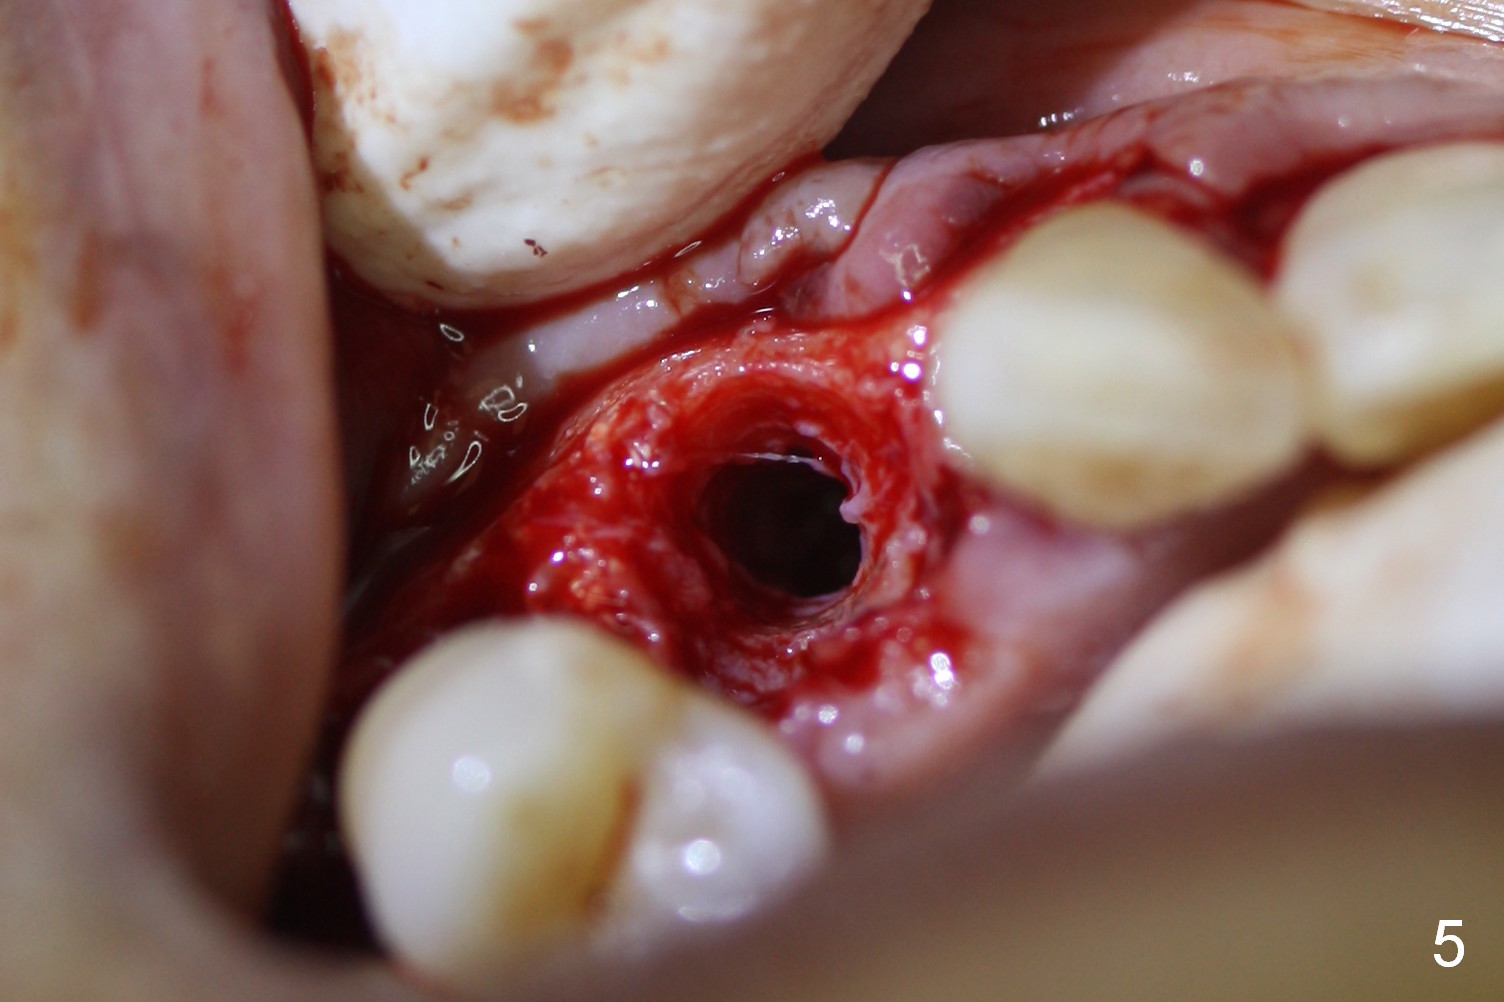

Four months post implant placement, the immediate provisional (Fig.1 P) has mobility with tenderness and perforation at the cervix (^). When the provisional is removed, the buccal plate bulging is more evident (Fig.2 arrowheads). The latter is apparently caused by bone expansion associated with implant placement (Fig.3 black *), since the bulging is not so obvious in a preop CBCT 3 D image (Fig.4 *). There is a layer of fiber granulation tissue (Fig.3 white *) around the mobile implant (I). More fiber tissue is noted when the implant is removed (Fig.5). A new osteotomy is created in the palatal wall of the existing implant site with 2 mm pilot drill, followed by 2.5 and 3 mm reamers. As a 4.5x17 mm tap is being inserted (Fig.6 T), it is deviated buccally. Reamers are re-used to try to remove more palatal bone to let the implant be placed more palatally. When a 4.5x17 mm tissue-level implant is placed (Fig.7,8 I with insertion torque >60 Ncm), there is a small buccal gap (Fig.8 *). A 20° angled abutment (Fig.7,8 A) is placed. An immediate provisional is fabricated with cosmetic satisfaction.